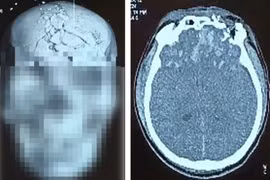

Khoa Hồi sức Thần kinh, Bệnh viện Trung ương Quân đội 108 vừa tiếp nhận điều trị cho nam bệnh nhân 45 tuổi bị thương tích nặng vùng đầu, mặt do pháo nổ.

Người đàn ông 45 tuổi bị thương tích nặng vùng đầu, mặt do pháo nổ

Trong quá trình chuẩn bị châm lửa cho dàn pháo tự chế, một quả pháo bất ngờ phát nổ, khiến bệnh nhân bị thương tích nghiêm trọng.